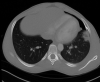

Non-traumatic complications of a solitary rib osteochondroma; an unusual cause of hemoptysis and pneumothorax

Osteochondromas are a very common and usually asymptomatic entity which may originate anywhere in the appendicular and axial skeleton. However, the ribs are a rare site of origin and here they may prove symptomatic for mechanical reasons. In this case report, we describe an unusual case of a symptomatic osteochondroma of the rib secondary to its location and unique shape, ultimately requiring surgical intervention.